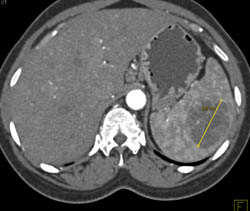

Splenic Hemangioma